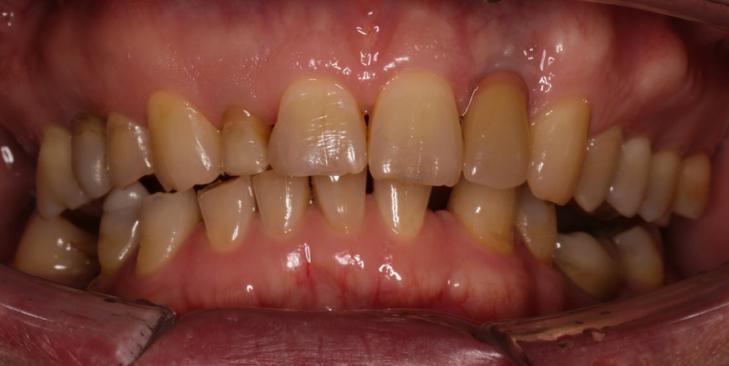

Симптомы повреждения эмали

- Гиперчувствительность.

- Изменение цвета.

- Шероховатость (неровности и шершавость).

- Боль при жевании и надавливании.

- Появление темных пятен.

К чему приводит повреждение эмали

- Повышенная чувствительность: появляется болезненная реакция на любые внешние раздражители (горячее, холодное, сладкое и кислое).

- Кариес: через кариозные полости опасные бактерий проникают вглубь зуба.

- Эстетические проблемы: истонченная эмаль часто выглядит тускло и больше не радует здоровой белизной.

- Трещины и сколы.